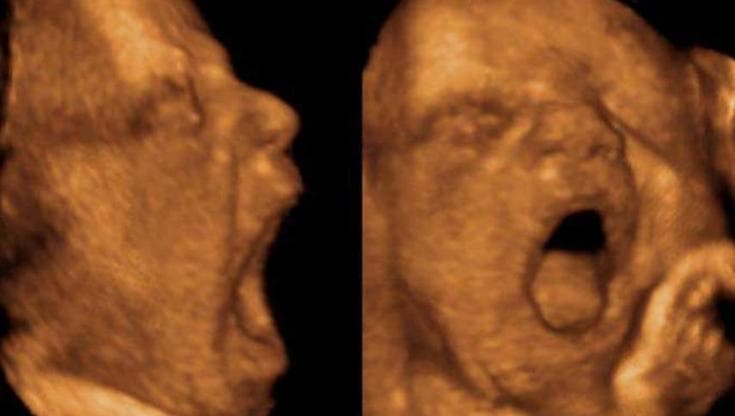

Chi sbadiglia molto nella pancia di mamma peserà un po’ di meno

Uno studio dell’università di Ferrara su Plos One ha analizzato 32 feti sani con ecografie 4D. Contribuendo al dibattito scientifico sulla grande domanda: a che cosa serve lo sbadiglio?